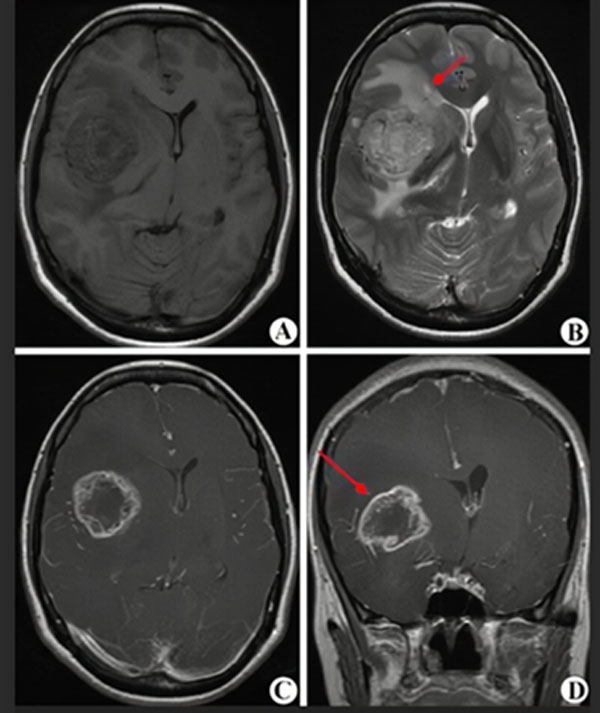

MRI(核磁共振)是一种无创伤的影像学检查,对脑肿瘤敏感性较高,大约1-2天可以拿到结果,是诊断和评估治疗效果的首选。但准确性只有80%-90%,不能作为确诊的最终依据。

(图A-D显示为高级别胶质瘤的核磁表现,红箭头指示肿瘤所在)

胶质瘤最终确诊还要依靠立体定向穿刺或开颅手术等有创操作,取得病变组织,由病理科医生确认病变是否为胶质瘤以及胶质瘤的级别,这一过程大约需要7-10天。